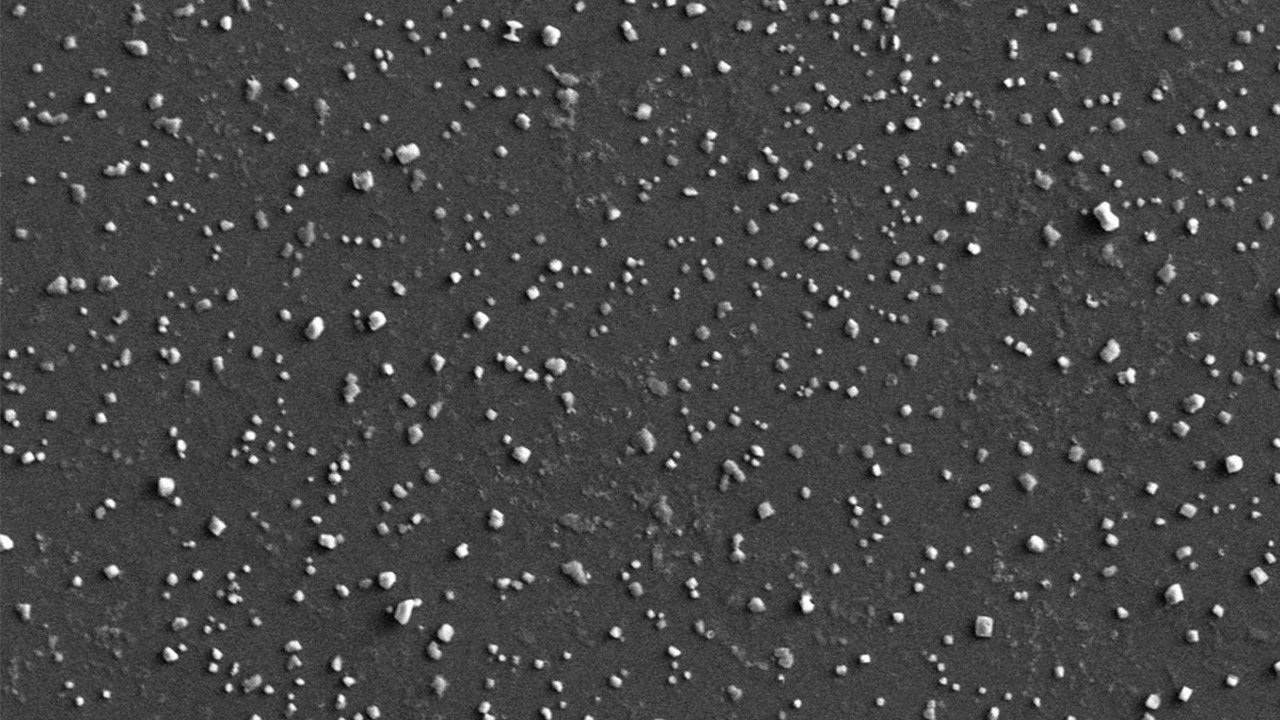

شمارش زیست‌شناساگرهای سرطانی با استفاده از نانوذرات و SEM

ICTPRESS-پژوهشگران با استفاده از نانوذرات طلا و میکروسکوپ SEM روشی برای تشخیص سریع و زودهنگام سرطان ارائه کردند. در این روش تراشه‌ای عامل‌دار شده برای جذب نانوذرات به‌کار گرفته می‌شود که در نهایت با SEM می‌توان میزان زیست‌شناساگرهای بیماری را شمارش کرد.